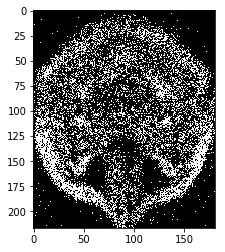

然后通过使用二项分布将每个像素二值化:

binarized_brains = np.random.binomial(1, (normalized_brains))

绘制的结果看起来正确:

0像素强度代表黑色(背景),1像素强度代表白色(脑组织)。